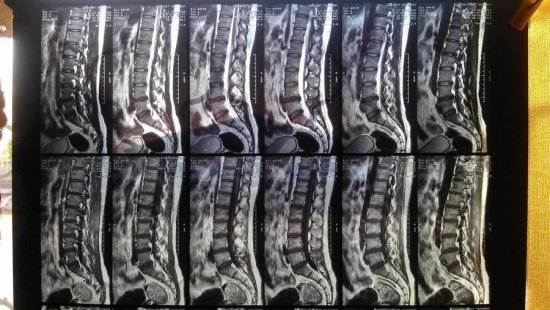

Если возникает болевой синдром поясничного отдела позвоночника, то часто причиной является остеохондроз. Пациента болит спина в области крестца, поясницы, болевые ощущения иррадиируют в нижние конечности. В спине человек почувствует перенапряжение, она будет скованной. Иногда чувствительность нарушается. Такое напряжение приведет к тому, что позвоночник потеряет гибкость, двигательная активность затруднится.

Болевые ощущения также возможны при грыжах между позвонками поясничного сегмента

Часто патологические изменения крестцового и копчикового сегмента при рентгенологическом исследовании не проявляются